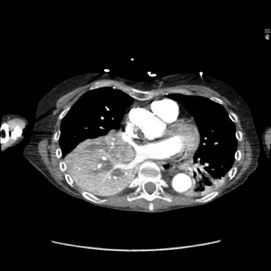

The patient was a 40-year-old white woman with a medical history significant for asthma, obstructive sleep apnea, and Down syndrome and who presented with dyspnea and fevers up to 102°F. She had recently completed an outpatient course of azithromycin, but she presented to an outside hospital for worsening shortness of breath despite this therapy. At the outside hospital, a computed tomography (CT) scan of the chest revealed a 3.7-cm heterogeneously enhancing mass that obstructed the bronchus intermedius with right middle and lower lobe consolidation (Figure 1a). The coronal thoracic CT scan demonstrated right middle and lower lobes that were atelectatic and consolidated with extensive and diffuse secondary mucous plugging (Figure 1b). Laboratory examination results at this time were significant for a white blood cell count 16.5x103/µL, sodium level of 133 mEq/L, potassium level of 3.2 mEq/L, serum creatinine level of 0.54 mg/dL, calcium level of 11.7 mg/dL, and lactic acid level of 2 mmol/L. She was transferred to the presenting institution for further evaluation and management.